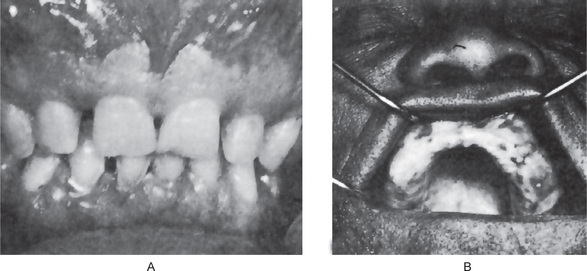

The maxilla exhibits progressive enlargement, the alveolar ridge becomes widened and the palate is flattened (Figs. 17-29, 17-30). If teeth are present, they may become loose and migrate, producing some spacing. When the mandible is involved, the findings are similar, but not usually as severe as in the maxilla. As the disease progresses, the mouth may remain open, exposing the teeth, because the lips are too small to cover the enlarged jaw.

Figure 17-29 Osteitis deformans.

There is diffuse enlargement of the maxilla and thickening of the dentulous (A) and edentulous (B) alveolar ridge. In addition, tipping of the teeth due to enlargement of the maxilla is obvious. (B, Courtesy of Dr Robert J Gorlin)

Figure 17-30 Paget’s disease.

Note the enlargement on the right maxilla. The patient was unable to use his denture.